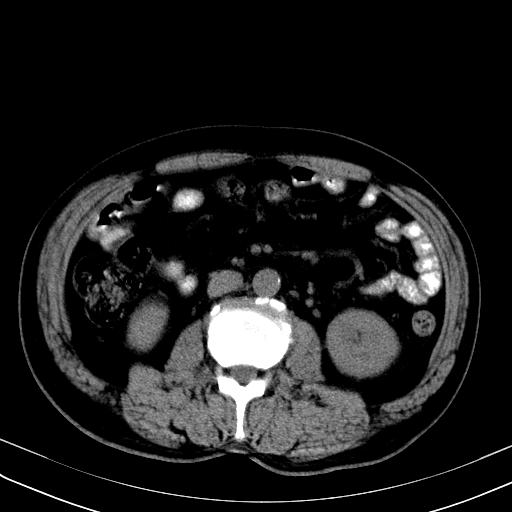

经典?纵膈多发肿大淋巴结。腹膜后未见异常。

还见胃窦壁增厚!转移亦有可能!

大家看看肝脏右叶片状低密度影是什么改变啊?

淋巴瘤?肝脏请增强后说啊

多发肿大淋巴结影,肝内改变需结合强化观察

多发肿大淋巴结影,肝内改变需结合强化观察。